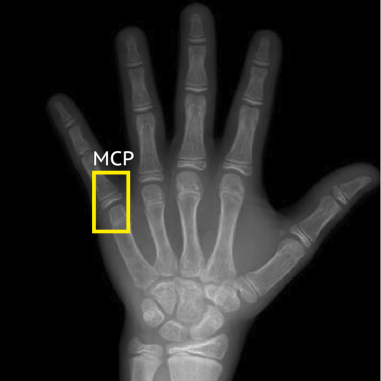

Evaluating Out-of-Distribution Generalization. Existing benchmarks primarily assess spatial understanding through visual question answering (VQA) and common sense reasoning [87, 157, 132]. However, we argue that evaluating model performance on compositional reasoning benchmarks alone does not effectively measure generalization to out-of-distribution tasks. Moreover, current spatial understanding and grounding benchmarks (e.g. RefCOCO [155] and OdinW [82]) typically evaluate performance on classes commonly found in internet pre-training. We demonstrate that such benchmarks artificially inflate model performance and are not representative of many real-world applications (cf. Table 1). To address this limitation, we introduce RF100-VL, a large-scale detection benchmark comprised of multi-modal datasets from diverse domains (cf. Fig. 1). Importantly, we carefully curate RF100-VL such that it cannot be solved by simply prompting state-of-the-art models with class names. Specifically, we include datasets where classes are labeled using scientific names (e.g. liver fibrosis and steatosis), acronyms (e.g. DIP and MCP), context-dependent names (e.g. detecting a block vs. set in the context of volleyball), material properties (e.g. paper vs. soft plastic), and diverse imaging modalities (cf. Fig. 2). We posit that models must leverage multi-modal contextual information (presented in the form of multi-modal annotator instructions) to effectively align to target concepts in RF100-VL.